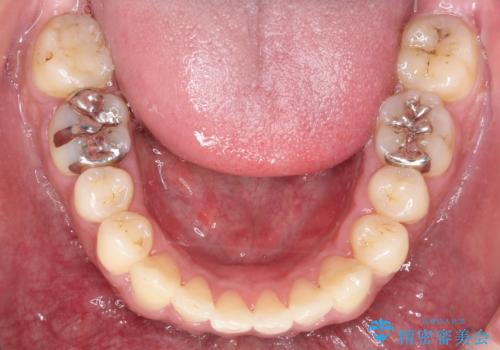

- 出っ歯が気になるとのことで来院されました。

上顎の前から4番目の歯を両側、合計2本抜歯して矯正する計画としました。

目立たない装置がご希望でしたので、上下裏側ワイヤー装置を選択されました。

裏側矯正は目立たないという利点がありますが、歯ブラシが非常に難しいなどのデメリットもあります。